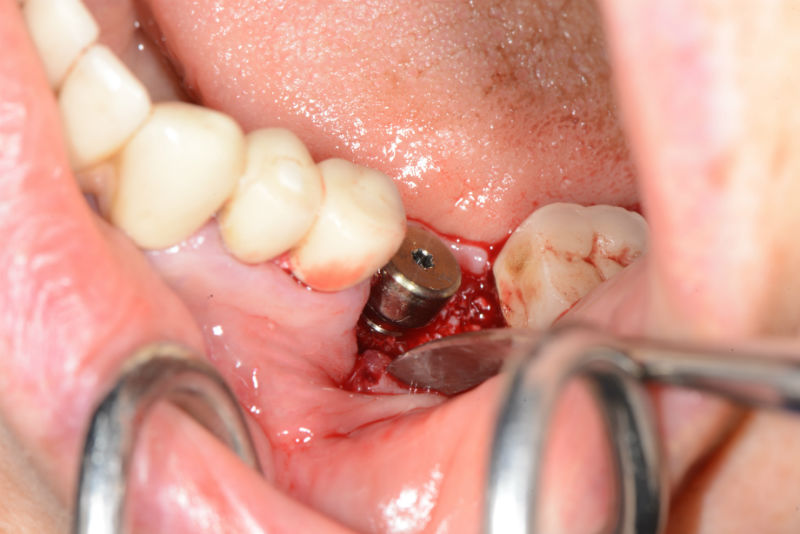

- методика на откритото имплантиране без ламбо – защото тогава хирурга няма реална визуализация на анатомията на костта.

- методиката на имедиатното /непосредствено след изваждане на зъбите/ поставяне на зъбни импланти – защото тогава вероятността на отклонение на дриловете по време на хирургичната препарация на имплантната ложа е много вероятна поради различната костна плътност, в резултат на това зъбните импланти няма да са в желаната от нас позиция.